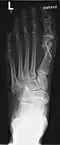

Hammerzehen nach der operativen Korrektur; deutlich sind die verkürzten dritten Glieder der drei inneren Zehen erkennbar (Operation nach Hohmann). Bei dieser OP wurde auch der Hallux valgus korrigiert. -

Hammerzehe am mittleren Zeh